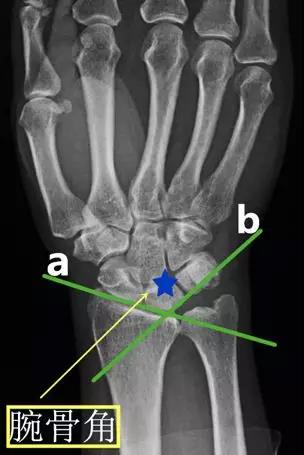

- 腕骨角:在腕关节正位片上分别作手舟骨、月骨的切线和月骨、三角骨的切线,此两线的夹角。

- 正常值:130°

- 临床意义:腕关节骨折、脱位时腕骨角增大;腕骨角减小见于Madelung 畸形和卵巢发育不全。